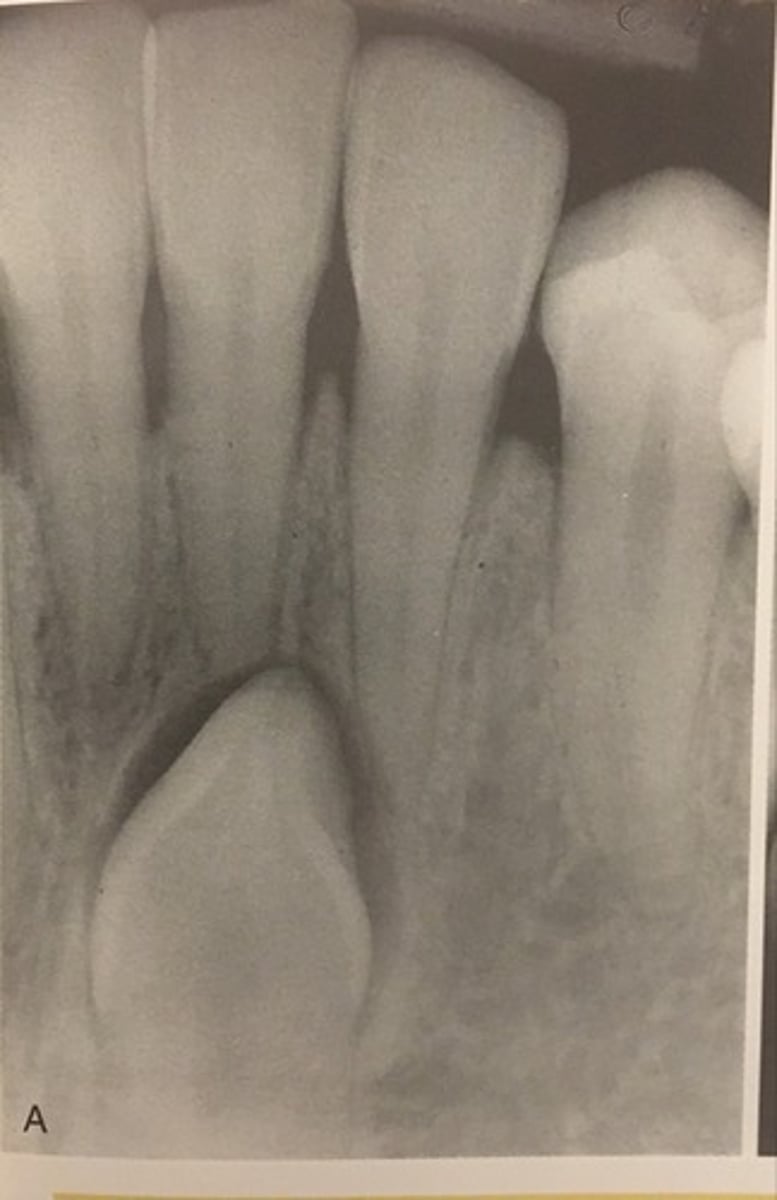

Diagnose dentinogenesis imperfecta radiographically

(on 2024 exam)

- bulbous crowns

- cervical constriction

- thin roots

- early obliteration of root canals and pulp chambers